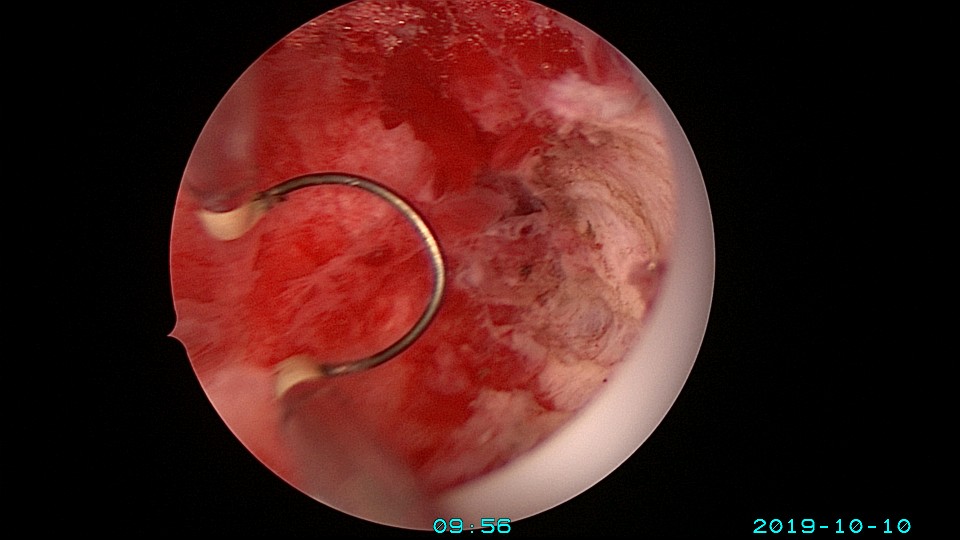

患者26岁,G1P0 ,2019年9月门诊宫腔镜检查发现宫腔重度粘连,2019年10月住院宫腔镜分粘,恢复宫腔形态,显露双侧输卵管开口。2019年11月宫腔镜二探取球囊,宫腔形态正常,双侧输卵管开口可见。2021年3月发现自然妊娠,后因先兆流产、胎心弱在当地医院险些清宫终止妊娠,病人电话咨询我,嘱病人千万不要急着清宫,立即到我院复查,心管搏动良好,住院保胎成功,2021年11月,39周孕剖宫产分娩。2023年7月,再次自然妊娠,39+3周孕剖宫产分娩。现31岁,G3P2。